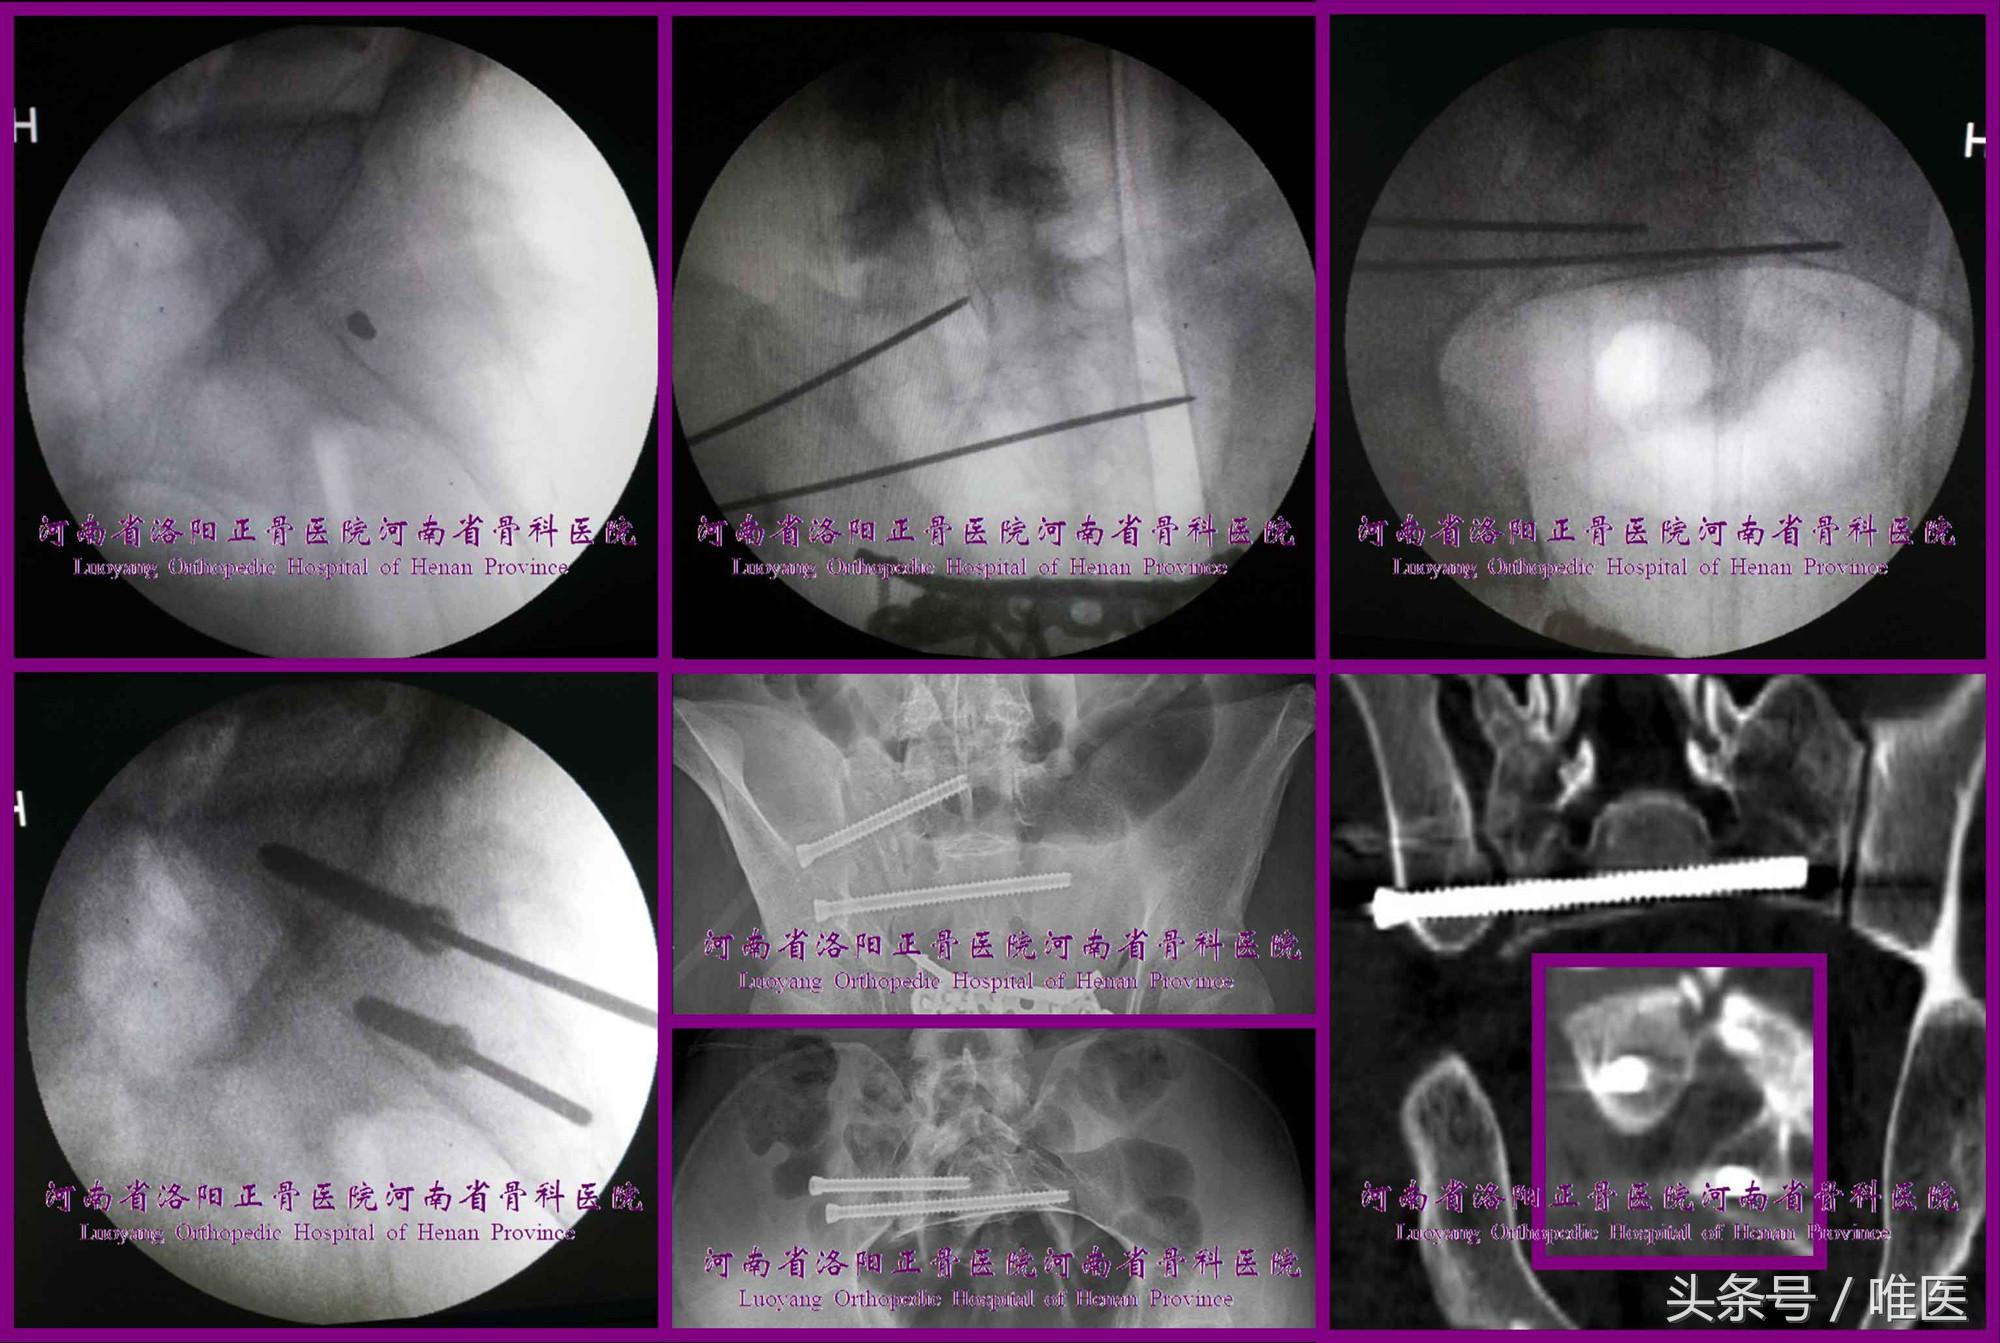

2. 骶2骶髂螺钉的置入技术

术前测量确定骶2节段是否存在安全置钉空间。如有安全空间,则按蔡鸿敏等所描述的置钉技术[22]进行置钉操作。(图13)

(1)确定进钉点 透视出标准骶骨侧位像,在此像上识别出骶神经根管前缘线、骶椎体前缘线、骶前孔上下缘等影像结构进而确定骶2节段的平向安全通道,将进钉点确定在其内。

(2)调整导针 将导针调整成一个点后轻浅打入骨质。

(3)确定导针的深度及指向 导针在骨盆出口位上应平行于上终板(或骶1双侧骶前孔下缘的联线),位于骶1及骶2骶前孔的中间(最少应打入椎体相对致密的骨质内,根据需要可打穿对侧髂骨外板)。骨盆入口位并非必须。

需要特别注意的是:当导针的进钉点未能成功调整成一个点并维持,则骨盆入口位亦不能提供可靠的指导,原因在于骶1/2椎体前缘存在上述三种关系,又在于骶1入口位及骶2入口位尚无可操作性。故为了避免骶髂螺钉突破骶2椎体前缘、骶2神经根管而需要再次透视标准骶骨侧位像确定螺钉位于骶2椎体前缘的后侧、骶2神经根管前缘线的前侧。

(4)置入骶髂螺钉:同上。

图13. 变异型上骶段骶2骶髂螺钉置入示例。